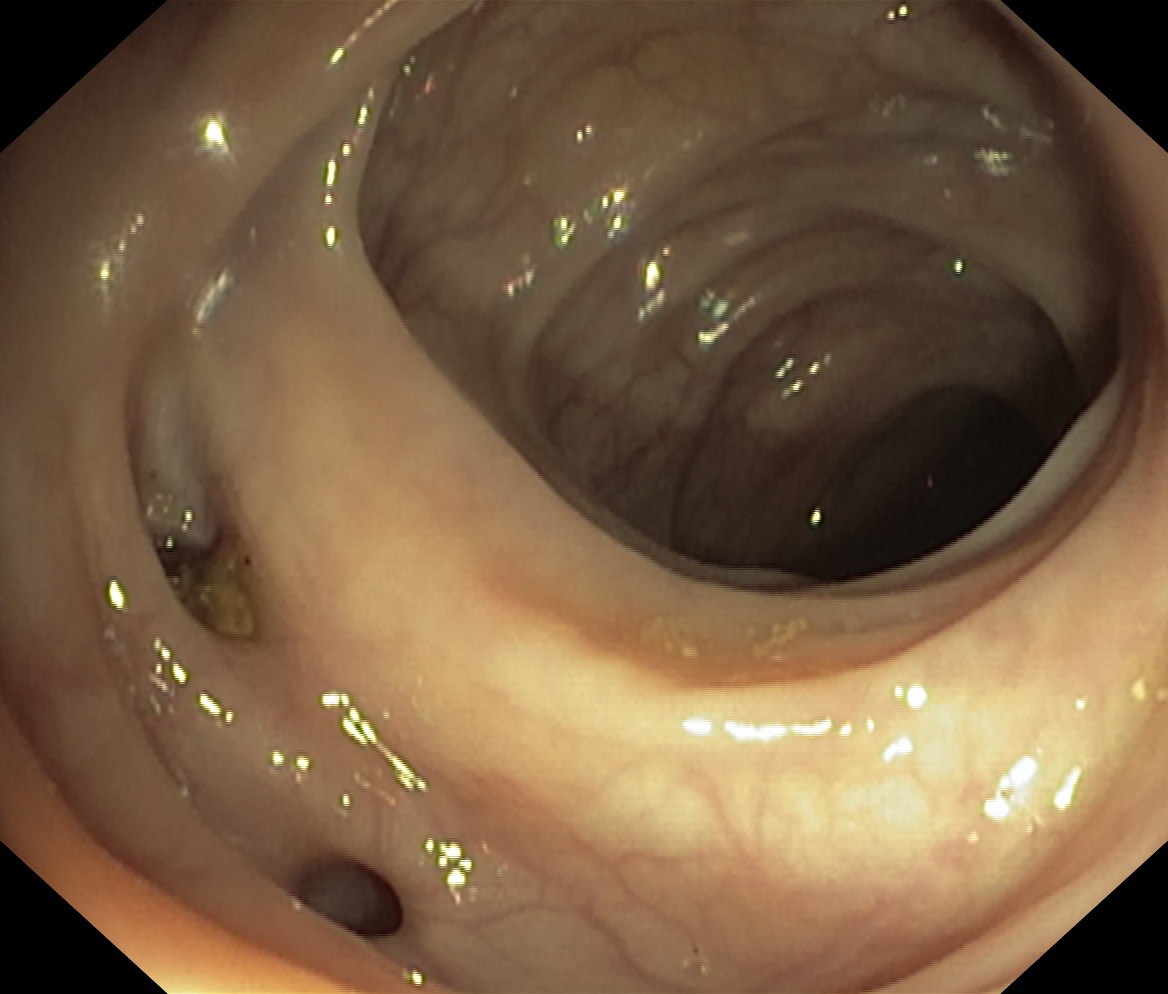

Uchyłki